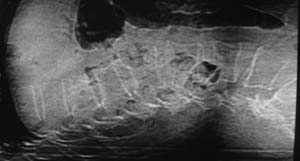

t12、l1椎体楔形变。老年骨质疏松症。

标绘图示:第十二胸椎级第一腰椎椎体楔形改变。ct扫描示:第十二胸椎椎体骨质结构紊乱,并可见一囊状低密度影,边缘可见硬化,椎体皮质完整。

考虑:第十二胸椎陈旧性骨折、许莫氏结节。